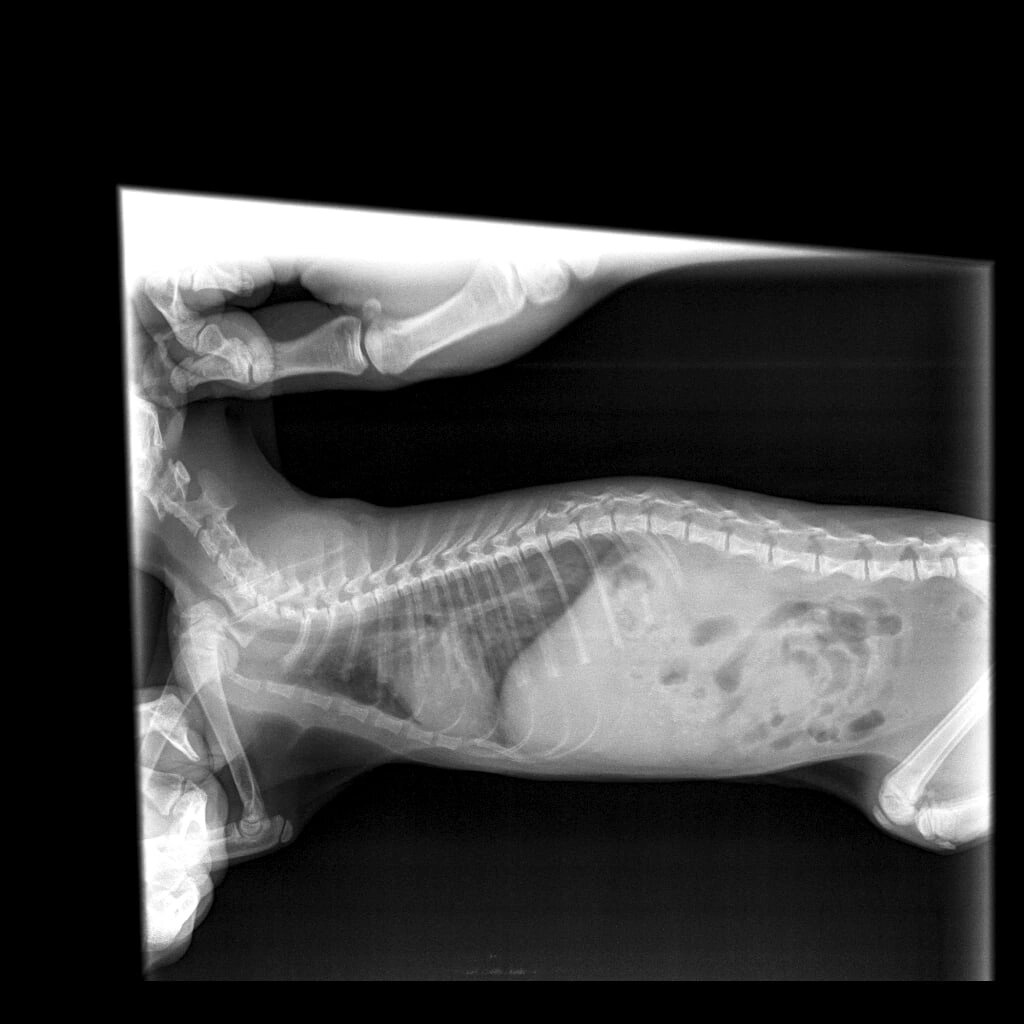

18/84 дней ФИП

Пневмония??? 😱🥺😭